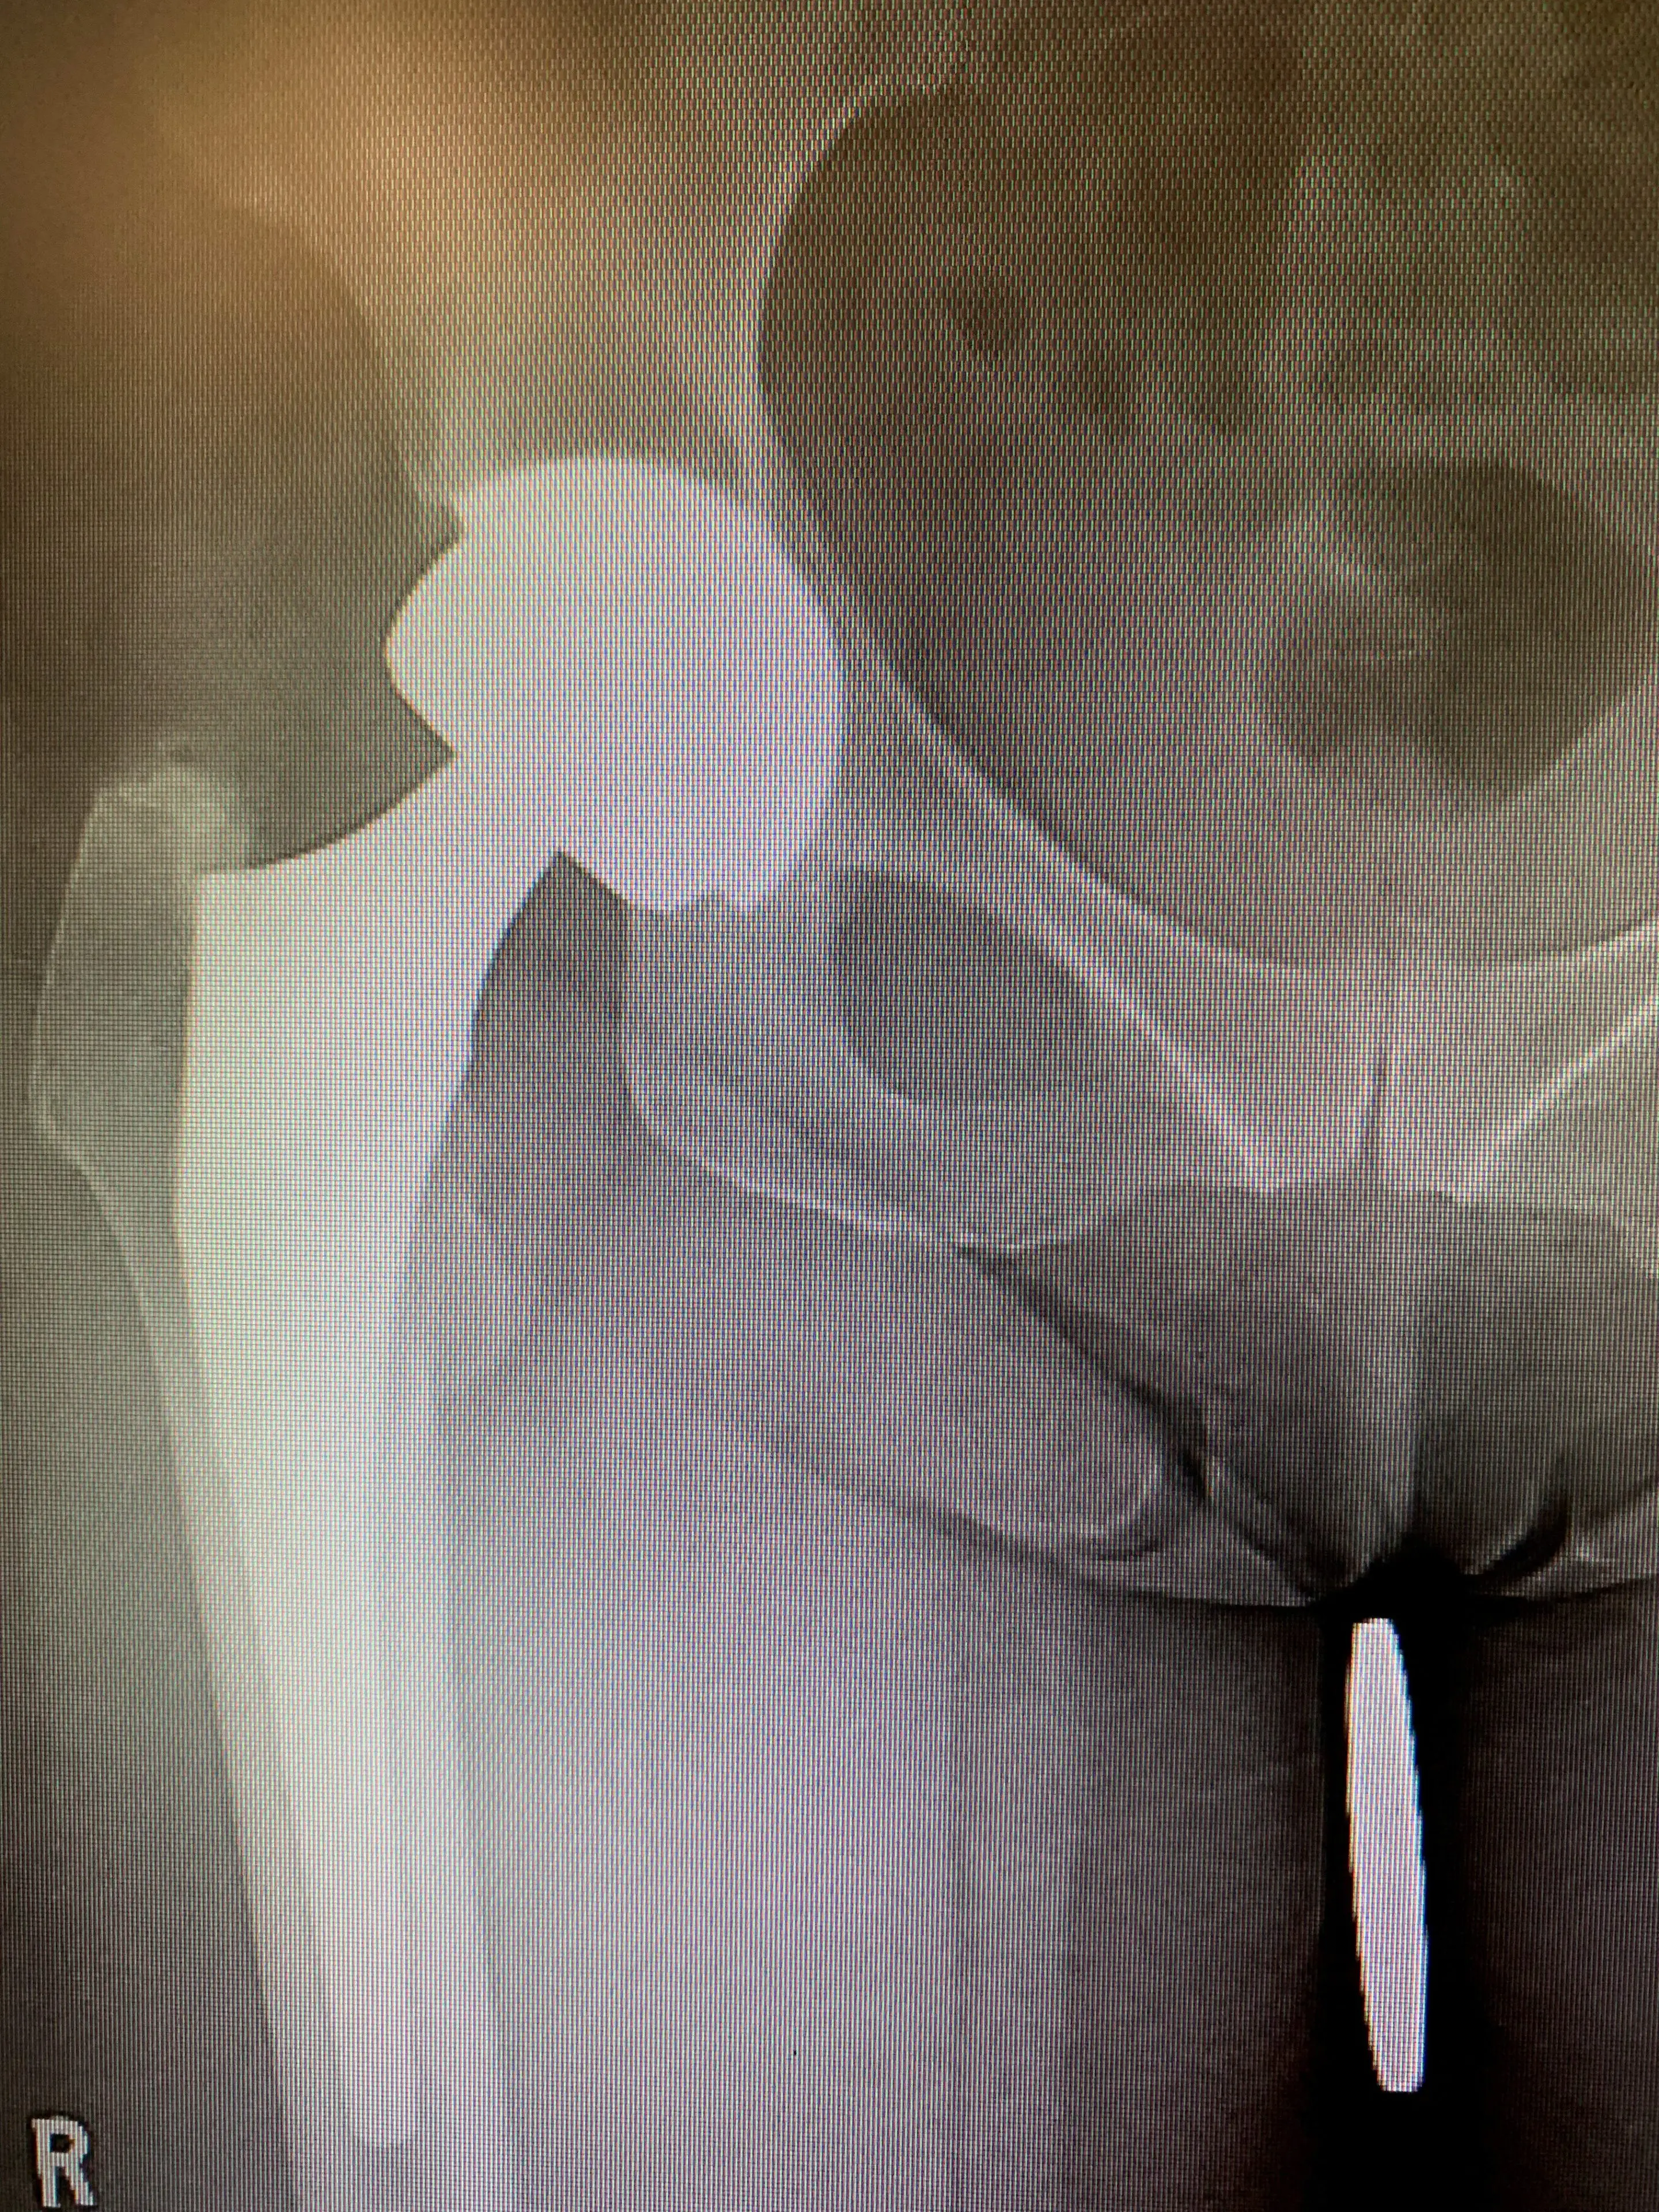

She accepted and consented, and we planned for her to receive surgery as soon as possible. We performed a posterior approach – the approach used for her first hip replacement and exposed her artificial hip fully. We dislocated it and used special instruments to first remove her acetabular liner, and then her acetabular component. We observed minimal bone loss, and so placed a slightly larger revision acetabular component in its place, ensuring stability and leg length were both restored.

Mrs. IS recovered within 3 months of her surgery, and is back to being fit and active and pain-free in her right hip.